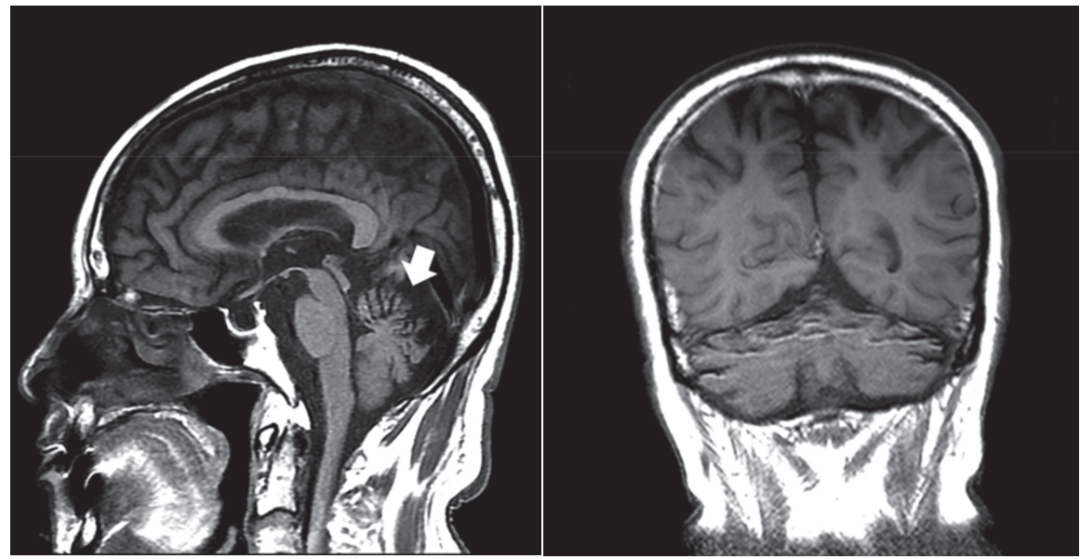

简称MBD,是一种罕见的以胼胝体脱髓鞘和坏死为主要病理特征的慢性酒精中毒相关性疾病。这种病的临床表现无特异性,急性起病者可出现严重的意识障碍和认知损害,常危及生命;慢性起病者主要表现为进行性痴呆。

急性期典型影像学表现为“三明治征”,即:矢状位上的病变主要位于胼胝体中层,上层和下层正常。以胼胝体全段受累更为常见。急性期后,胼胝体异常信号逐渐消退。

慢性期表现为胼胝体萎缩,伴局灶性长T1、T2信号,可能反映了进行性脱髓鞘、局灶性坏死和囊变。如果病变出现在胼胝体外,则以皮质下白质最为多见。

颅脑MRI矢状位FLAIR示胼胝体压部高信号(A)

DTI示同一部位胼胝体横向纤维受损(B)

DWI和ADC示胼胝体压部细胞毒性水肿(C、D)

颅脑MRI、DWI示:

双侧大脑半球皮层下白质、

胼胝体、双侧小脑中脚高信号

颅脑MRI示小脑萎缩

尤其是在小脑蚓部和半球的的前部